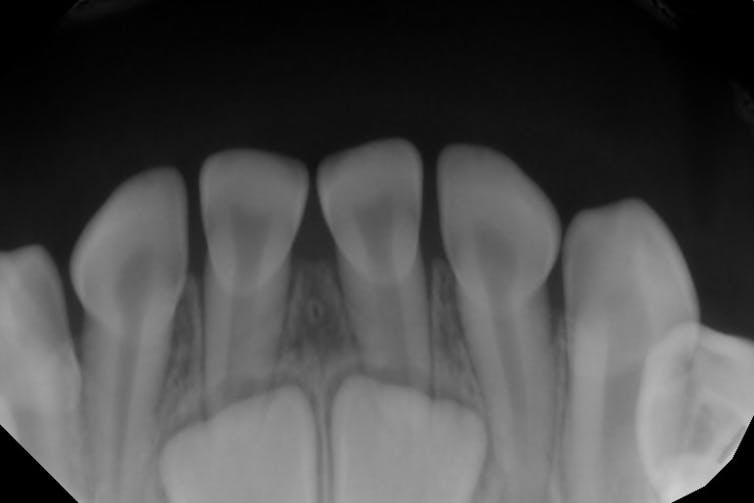

Most people are born with no teeth showing in their mouths at all, even though your baby teeth start developing before you’re even born. Baby teeth usually start poking through the gums when you’re between 6 and 8 months old. Sometimes when dentists take X-rays to check for cavities or other problems, they can see adult teeth growing within the gums.

X-ray of a child’s mouth shows two adult teeth growing in the jaw below the visible baby teeth.

David Avenetti